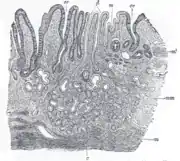

The GI tract is essentially a hollow tube connecting the mouth to the anus. The GI tract has a similar layout through out its length:

- An inner mucosal layer with an epithelial lining

- A submucosal layer

- A thin layer of muscle , the Muscularis Mucosa is at the junction of the mucosal and sub mucosal layers, outside this are the nerves of the mucosal plexus

- A muscular layer with an inner circular muscle layer and an outer longitudinal layer

- Between the muscles are the nerves of the myenteric plexus

- A serosal layer which is continuous with the mesentry

This is illustrated graphically here:

Mucosa

The mucosal layer consists of a epithelial layer, and its underlying supportive tissue, the Lamina Propria. It is separated from the submucosal layer by the Muscularis Mucosa. The epithelial layer varies from section to section of the gut. In the oesophagus it is a non-cornified stratified squamous epithelium; in the stomach it is mainly mucosal cells; the small intestine and large intestine are characterized by absorptive cells, with many mucous producing goblet cells. In the absorptive sections of the intestine, the surface are for absorption is greatly increased by finger-like projections into the lumen called villi, and the absorptive cells themselves also have small projections of microvilli, giving them the appearence of a brush border when viewed with a light microscope.

The lamina propria contains lymph and blood vessels which drain into larger vessels in the submucosal layer. Also in the lamina propria, particularly in the absorptive layers are numerous immune cells, wandering macrophages and lymphocytes, as well as aggregations of lymphoid tissue called called Peyers patches. By some estimates 80% of the body's lymphoid tissue is in the intestine.

The cell-to-cell junctions are of the epithelia are mainly tight junctions. In the stomach there are very little or no gaps between the epithelial cells, but in the absorptive sections there is a certain amount of 'leakiness' so that water and some solutes can go between the cells rather than through them. The degree of leakiness is variable and is to some extent under hormonal control.

Submucosa

The submucosa consists of connective tissue with larger blood and lymph vessels. It is separated from the mucosa by the muscularis mucosa. Also in the submucosal layer is the submucosal plexus, part of the enteric nervous system. The muscularis mucosa probably acts to propel the contents of the mucosal glandular lumens and crypts (see below) into the lumen and also to enhance contact of the cells with the contents of the lumen.

Muscular Layers

Consists of an inner circular muscle, and an outer longitudinal muscle. Between the two layers is the mesenteric plexus, also part of the enteric nervous system. In the stomach there is also an oblique layer of muscle fibers interior to these two. The musclar layers work in harmony to produce peristaltic contractions and segmental contractions.

Serosa

The serosa is a continuation of the peritoneal membrane. It is useful to think of the gut as being envaginated into the peritoneal membrane until it completely surrounds it. The double layer of membrane as it attaches to the gut is called the mesentery, and it contains the main vessels and the non-intrinsic nerve supply to the gut.